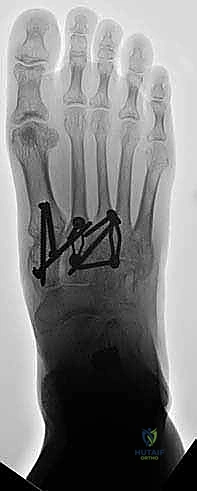

لضمان التحام العظام لتصبح عظمة واحدة صلبة، يجب تثبيتها بقوة هائلة حتى لا تتحرك أثناء فترة الشفاء. يتم استخدام مسامير معدنية متطورة (Screws)، أو شرائح معدنية خاصة (Plates)، أو دبابيس طبية متخصصة (Staples) مصنوعة من التيتانيوم الآمن على الجسم.

بعد التأكد التام من وضع العظام وثباتها باستخدام جهاز الأشعة السينية داخل غرفة العمليات (C-Arm)، يتم إغلاق الشقوق الج